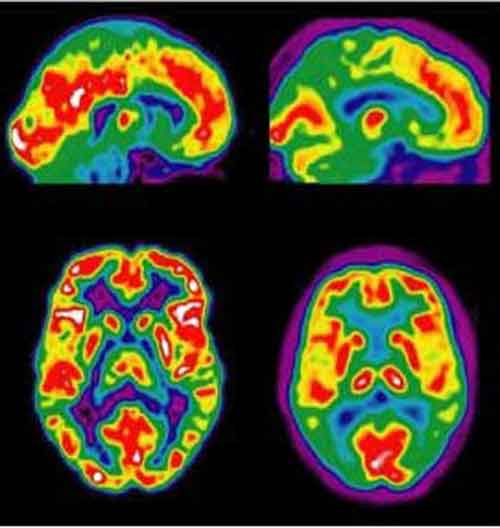

Gli studiosi dell’Alzheimer si concentrano sui primi stadi della malattia e sui problemi di memoria a breve termine.alzheimer Una nuova ricerca, tuttavia, suggerisce che i pazienti possono avere problemi molto presto anche nell’elaborazione del significato delle informazioni e con le informazioni basate sulle proprie conoscenze pregresse.

Problemi che possono tradursi in disagi molto ampi. Lo studio del The Feinstein Institute for Medical Research in Manhasset e’ stato pubblicato sull’American Journal of Psychiatry. Gli scienziati hanno valutato il deterioramento semantico in 25 pazienti con lieve peggioramento cognitivo (Mci), 27 con Alzheimer e 70 in salute. “Le ricerche ci hanno suggerito che l’elaborazione semantica era corrotta sia nei pazienti con Mci sia con Alzheimer: nonostante si trattasse di due stadi diversi della malattia, gli effetti di peggioramento dell’elaborazione del significato delle parole erano molto simili”, ha spiegato Terry Goldberg, fra gli autori dello studio.